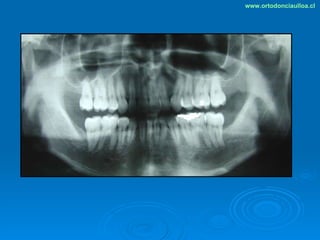

Este documento presenta dos casos clínicos de pacientes que recibieron tratamiento de ortodoncia. El primer caso fue de una paciente femenina de 14 años con apiñamiento dental y mordida cruzada que fue tratada mediante extracción de premolares y alineamiento dental. El segundo caso fue de un paciente masculino de 14 años con clase II esqueletal y desarmonía dentomaxilar que fue tratado con extracción de premolares y corrección de mordida. Ambos casos mostraron mejoría después de 3 años de tratamiento.